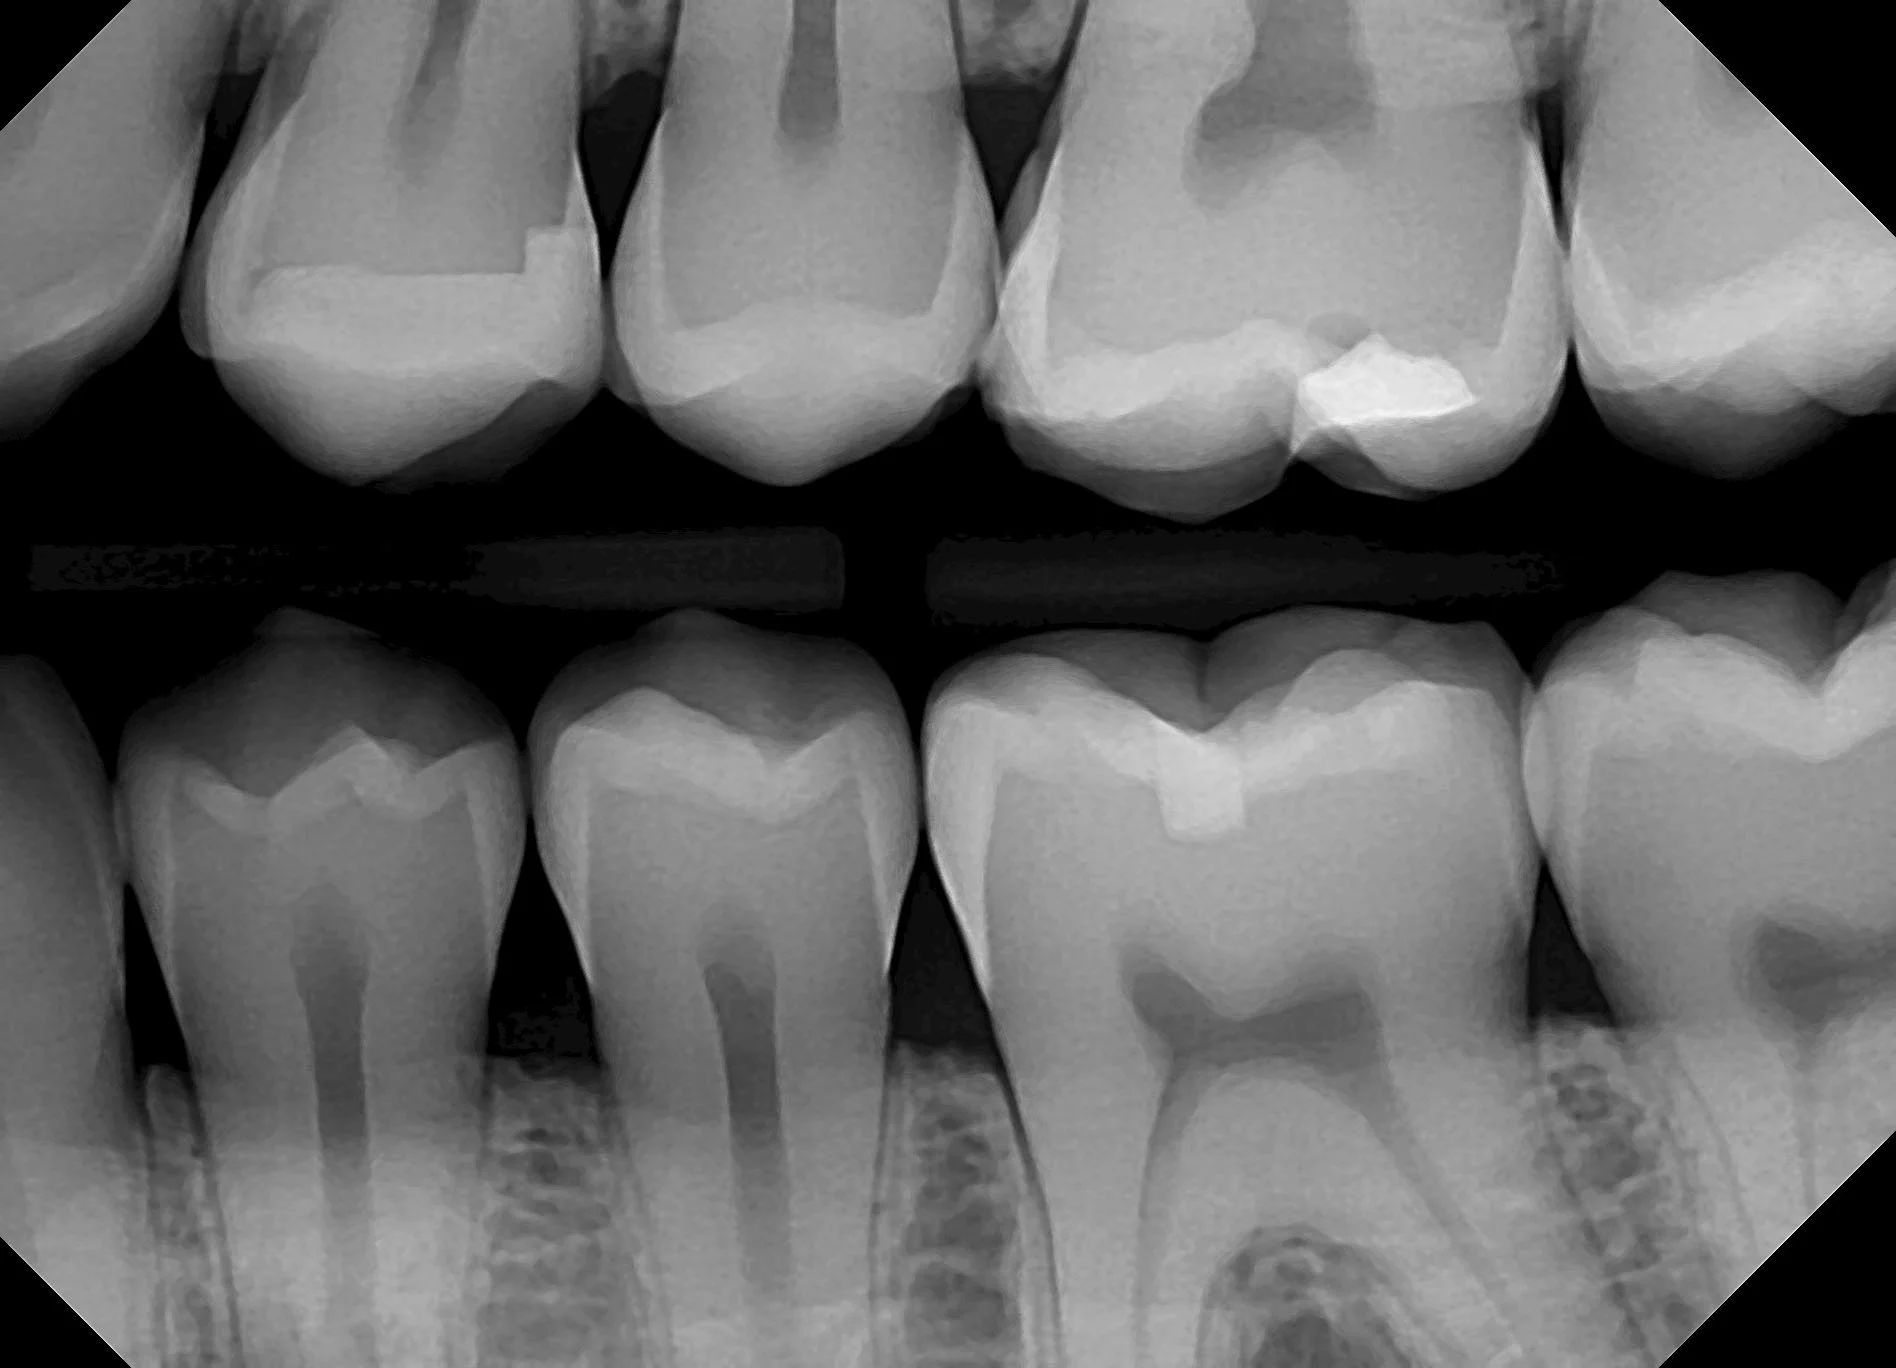

Erken teşhiste en büyük yardımcılarımızdan biri de röntgen görüntüleridir. Röntgen sayesinde gözle görülemeyen çürükler, gizli iltihaplar, kemik kayıpları ve kist gibi sorunlar fark edilebilir. Böylece sorun büyümeden, küçük ve basit işlemlerle çözüme ulaşmak mümkün olur.